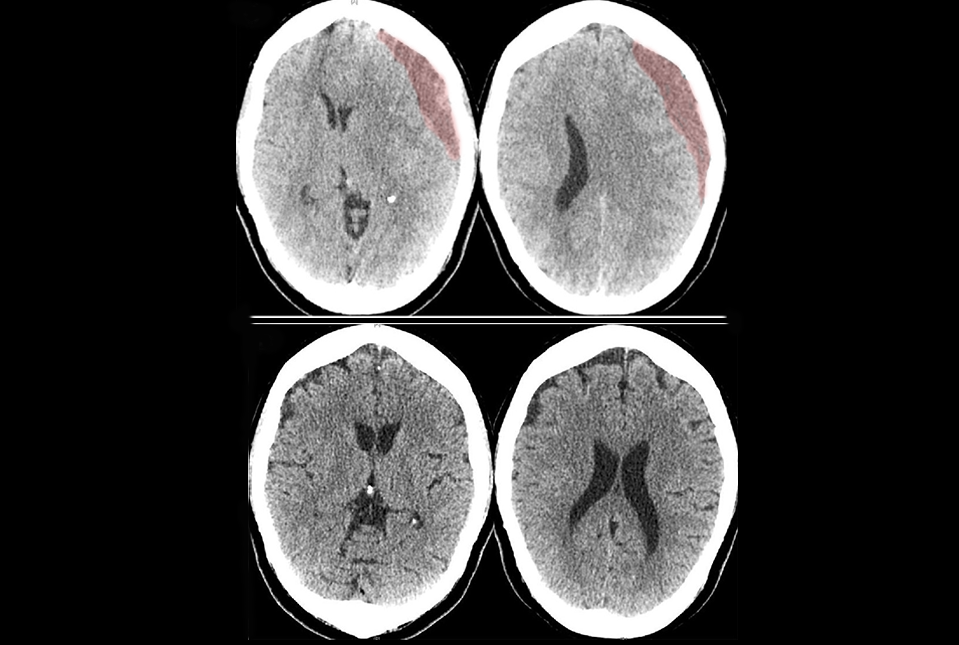

A novel combination of surgery and embolization used to treat subdural hematomas, bleeding between the brain and its protective membrane due to trauma, reduces the risk of follow-up surgeries, according to researchers at Weill Cornell Medicine and University at Buffalo. Embolization is a minimally invasive procedure that blocks specific blood vessels to stop abnormal bleeding.

Symptoms of subdural hematoma—including weakness, numbness, headaches, nausea, confusion or dizziness—can come on slowly over days or weeks, after a fall or other head injury. “For the last century, doctors have treated symptomatic subdural hematomas the same way; with surgery to create a small hole in the skull or removing a small section of skull to drain the blood,” Dr. Knopman said.

However, after a hematoma has been surgically drained, it recurs about 15% of the time, requiring another surgery and hospitalization. The hematoma recruits arterial blood vessels that keep it alive. “So even after you remove the blood, it can come back and require more surgery. This is particularly challenging for older patients, who are the most prevalent group suffering from chronic subdural hematomas,” Dr. Knopman added.

Dr. Knopman and Weill Cornell Medicine colleagues developed the MMA embolization procedure and published initial successful results in 2019. The procedure involves threading a small catheter into the middle meningeal artery that runs through the membranes covering the brain. The catheter delivers an embolic or clotting agent to block blood vessels feeding the hematoma. “By reducing the chance of the subdural hematoma from coming back, the need for hospital re-admission and another operation can be avoided,” Dr. Knopman said.